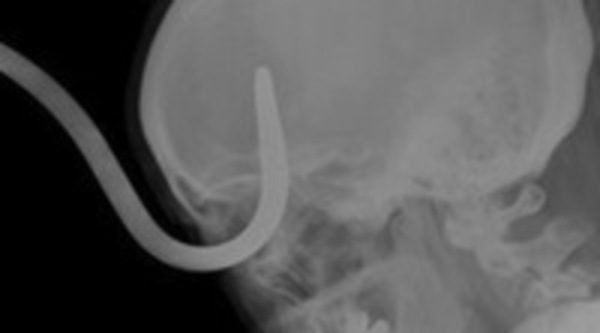

Visto que el tema médico tiene su público en la franja del late night, Discovery Max ha decidido probar la eficacia de este nuevo formato, 'Urgencias punzantes'. Desde verjas a piezas de aviones, de anillos de compromiso a una cubertería completos o cemento. El nuevo programa da la bienvenida a una realidad verdaderamente asombrosa: la de los artículos incrustados en el cuerpo humano.

La serie, integrada por seis entregas de una hora de duración cada una, narra los sucesos más extraños que acabaron con los protagonistas de la serie 'aseteados' por accidente y con una situación médica de riesgo extremo de complicada, aunque no imposible, solución. Situaciones bizarras y asombrosas que pueden enseñar no sólo a extremar las precauciones, sino a mantener el control cuando lo más incontrolable se apodera de las personas.

A través del testimonio de las víctimas, de declaraciones de testigos, recreación del suceso y el uso de impactantes imágenes generadas por ordenador, se verán las historias más inexplicables, inesperadas y sorprendentes.

El primer episodio muestra el caso de una niña escocesa que nunca imaginó que un inocente paseo por la calle acabase con una valla metálica clavada en su propia cara. Otro de los casos más llamativos es el de un jardinero que, tras un descuido con la máquina cortacésped, terminó con las tijeras de podar en su cráneo.